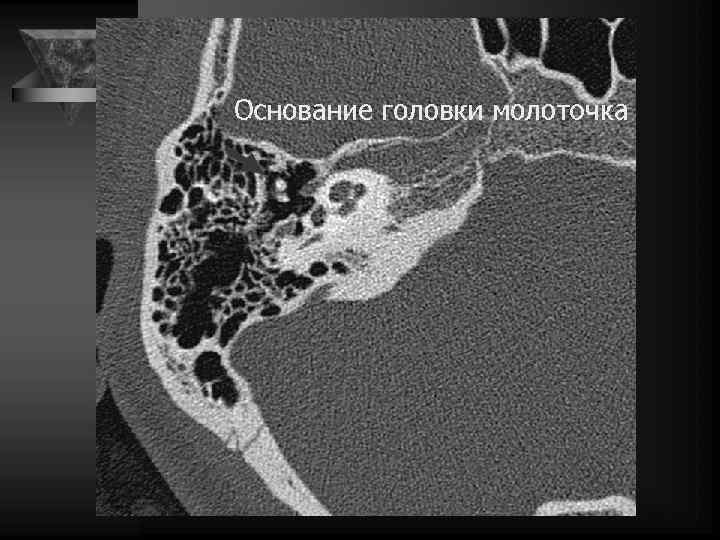

Молоточек 2 головка 3 шейка 4 рукоятка 5 передний отросток 6 латеральный отросток

Внутреннее ухо и верхушка пирамиды • Улитка: деминерал-я костной капсулы, спирал-й канал улитки и его просвет, оссификация • Преддверие и полукружные каналы, интактные стенки, оссификация • Внутр. слух. проход: расширение, неровн-ть контура, деструкция кости, стеноз • Канал лицев. нерва до коленч. ганглия. • Водопровод преддв-я и водопр. улитки. • Верхушка пирамиды: губчатая или пневматизирована, наличие секрета, наличие образований